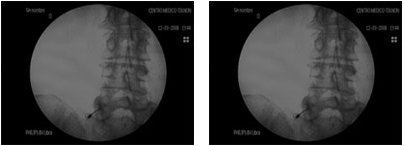

Els bloquejos terapèutics provoquen la interrupció de l'impuls nerviós i del concomitant reflex simpàtic i motor i provoquen analgèsia temporal, interrupció reflecteix i alleujament del dolor per un període més prolongat que la mateixa acció de l'anestèsic local. Tot això comporta que els bloquejos repetits constitueixin un tractament del dolor crònic. Són practicats sota fluoroscòpia i s'utilitza l'electroestimulació i el mitjà de contrast per verificar el nervi exacte que es vol bloquejar.

El bloqueig simpàtic lumbar és un procediment utilitzat per diagnosticar, disminuir o eliminar el dolor produït pels nervis autonòmics que són afectats per traumatismes, cirurgies o malalties vasculars.